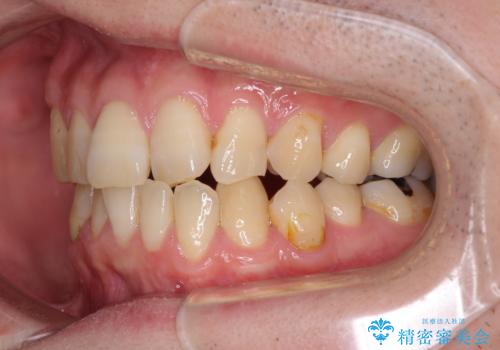

欠損のある歯列 インビザラインで整った歯並びに

- デコボコした前歯をセラミックできれいに揃えたいとのことで来院された患者様です。

歯を削って整えることは簡単ですが、健全な歯を削って後悔してからでは遅いため、矯正治療を提案しました。

はじめは矯正治療の期間が長いことに悩んでいらっしゃいましたが、ある程度整えば満足するだろうとのことで、インビザラインにて矯正治療を行うこととしました。

左上の犬歯が欠損しているため、正中の位置や奥歯の咬み合わせが理想的にならない点を了承していただきました。